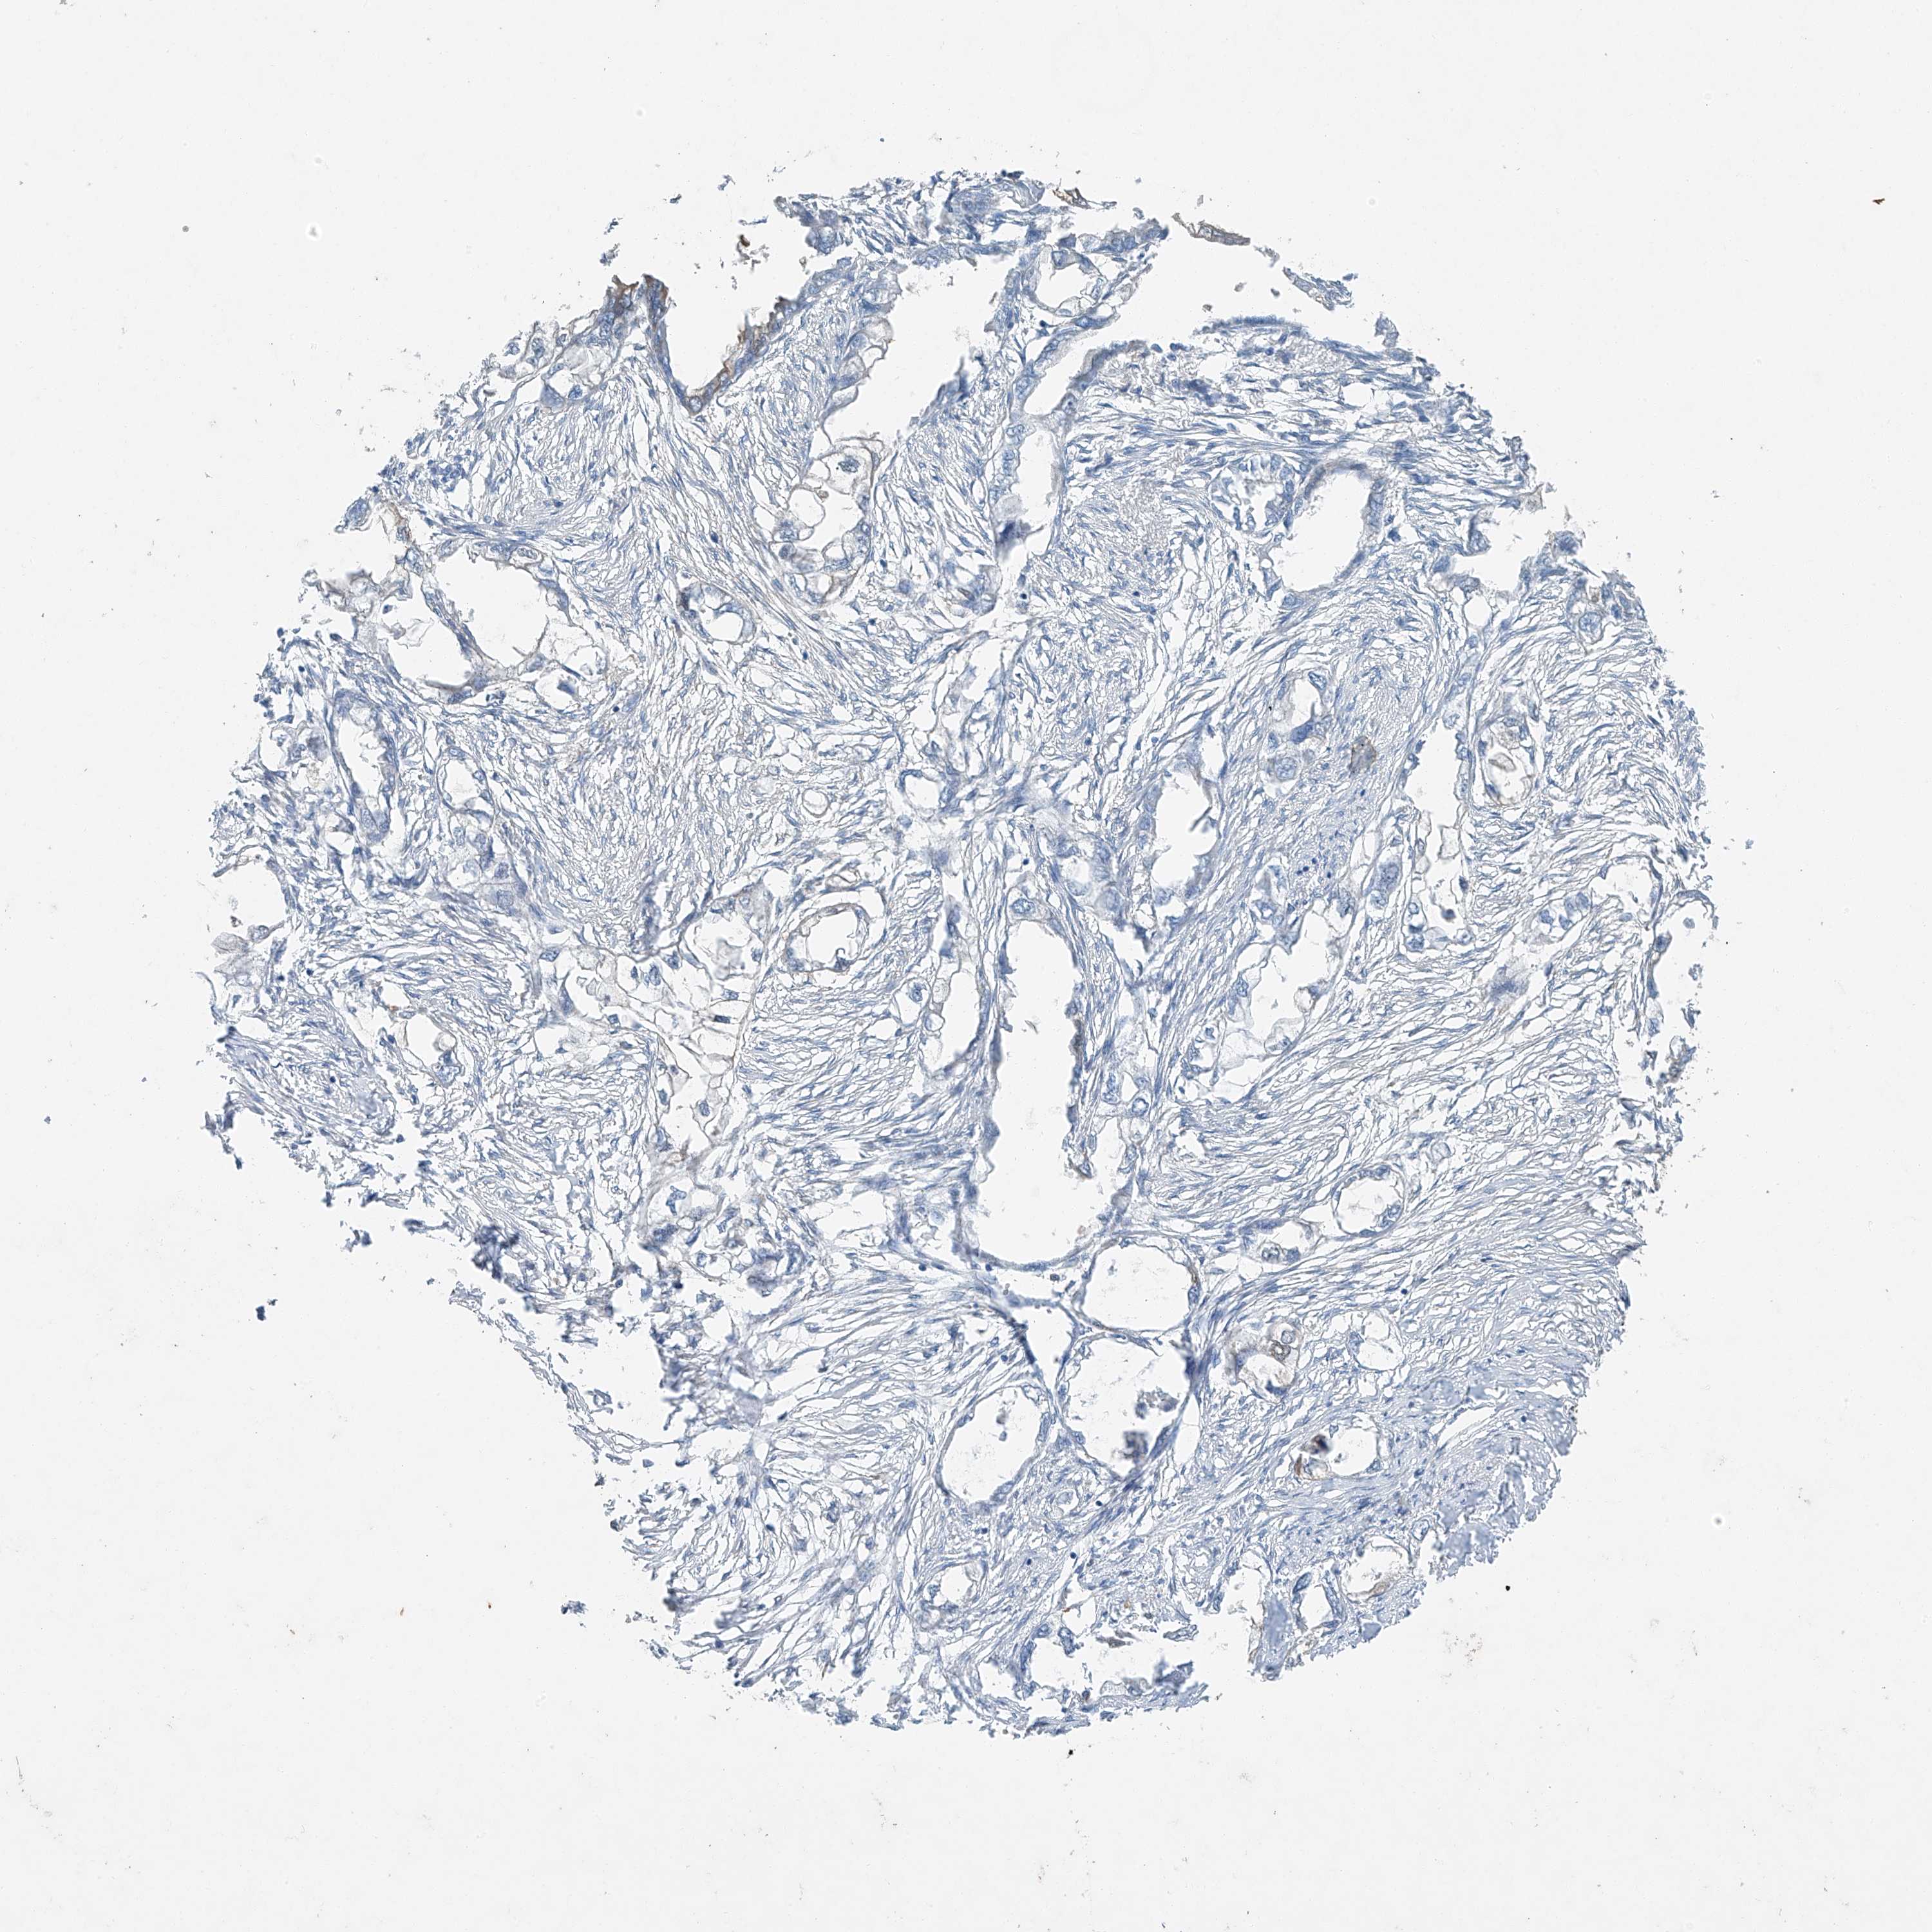

ENDOMETRIAL CANCER - Protein expressioni

A mouse-over function shows sample information and annotation data. Click on an image to view it in a full screen mode. Samples can be filtered based on level of antibody staining by selecting one or several of the following categories: high, medium, low and not detected. The assay and annotation is described here.

Note that samples used for immunohistochemistry by the Human Protein Atlas do not correspond to samples in the TCGA dataset.

Antibody stainingi

Antibody staining in the annotated cell types in the current human tissue is reported as not detected, low, medium, or high, based on conventional immunohistochemistry profiling in selected tissues. This score is based on the combination of the staining intensity and fraction of stained cells.

Each image is clickable and will lead to virtual microscopy that enables deeper exploration of all samples and also displays staining intensity scores, fraction scores and subcellular localization as well as patient and tissue information for each sample.

Antibody HPA031730

Antibody HPA031731

Antibody HPA031734

Staining

High

Medium

Low

Not detected

Intensity

Strong

Moderate

Weak

Negative

Quantity

>75%

75%-25%

<25%

None

Location

Nuclear

Cytoplasmic/membranous

Cytoplasmic/membranous,nuclear

Adenocarcinoma, NOS

Adenocarcinoma, metastatic, NOS